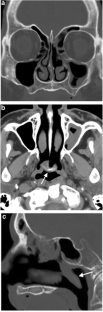

Nasotracheal intubation (NTI) is used for maintaining airway access during maxillofacial surgery or in cases of severe oral trauma. We describe a case of middle turbinectomy complication as a result of NTI. The purposes of this paper are to raise awareness of this complication and review associated imaging findings.

Fig. 2